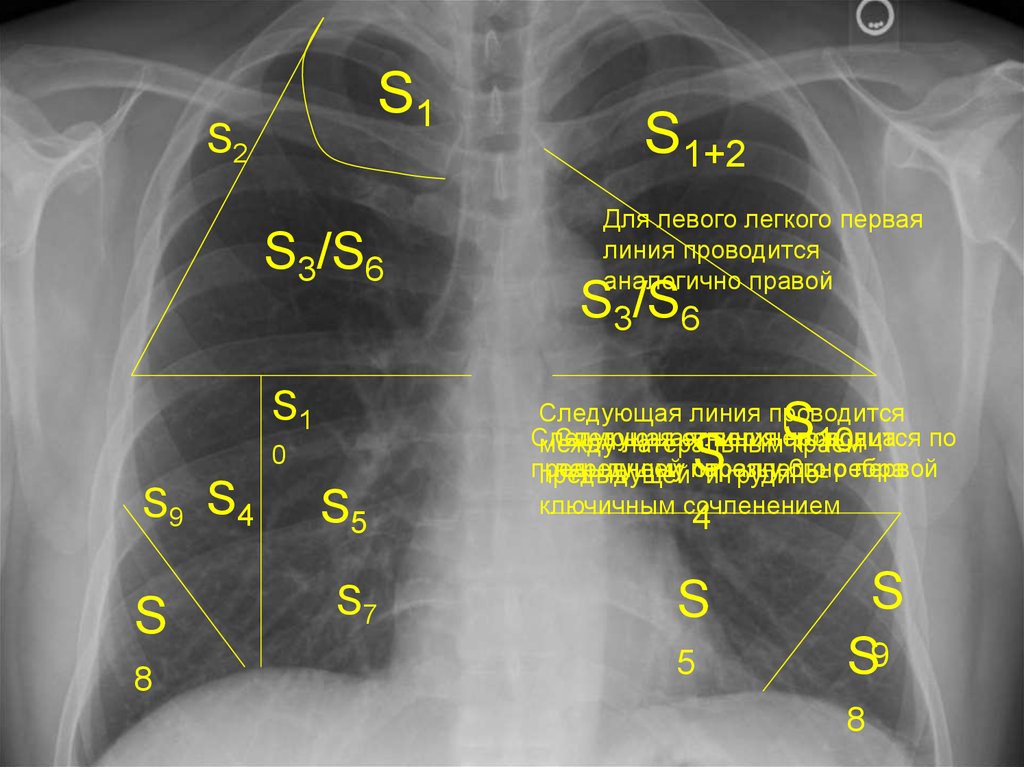

Анатомические изображения сегментов легких различных животных

Раздел: Другие животные